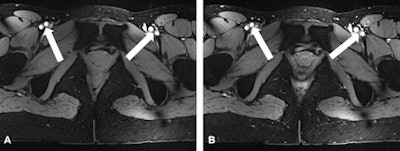

T2 turbo spin-echo imaging (A) of the female pelvis revealing good quality delineation of the zonal anatomy of the uterus. 2D FLASH post-contrast imaging (B) shows lack of enhancement of the ovarian cysts (arrows). The thin arrow in figure B marks a residual inhomogeneity artifact in the right gluteal muscle. All images courtesy of Dr. Lale Umutlu.

T2 turbo spin-echo imaging (A) of the female pelvis revealing good quality delineation of the zonal anatomy of the uterus. 2D FLASH post-contrast imaging (B) shows lack of enhancement of the ovarian cysts (arrows). The thin arrow in figure B marks a residual inhomogeneity artifact in the right gluteal muscle. All images courtesy of Dr. Lale Umutlu.Ultrahigh-field (7-tesla) MR systems have been successfully implemented for in vivo human imaging and are becoming increasingly established for structural and functional brain imaging at research sites worldwide, wrote Dr. Lale Umutlu, from the department of diagnostic and interventional radiology and neuroradiology at University Hospital Essen, and colleagues.

Nonenhanced (A) versus post-contrast (B) 2D FLASH imaging of the pelvis. Notice the equivalently high-quality delineation of the arterial and venous vasculature (arrows).

Nonenhanced (A) versus post-contrast (B) 2D FLASH imaging of the pelvis. Notice the equivalently high-quality delineation of the arterial and venous vasculature (arrows).For qualitative image analysis of pelvic anatomy, the researchers assessed uterine zonal anatomy and image impairment due to artifacts using a five-point scale. For quantitative analysis, contrast ratios between the junctional zone and myometrium were obtained for T2-weighted MRI.